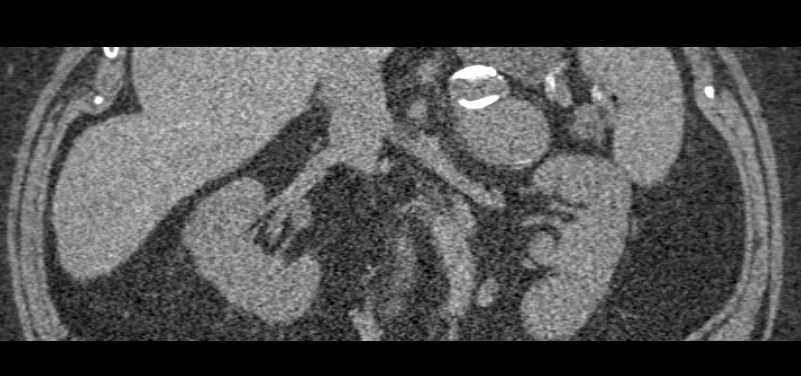

Old Adrenal Hematoma with Calcification